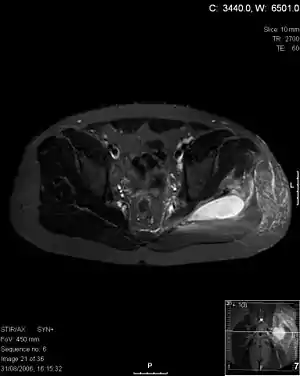

| Transverse T2 magnetic resonance imaging section through the hip region showing abscess collection in a patient with pyomyositis. | |

| Diagnostic method | Diagnostic method used for PM includes ultrasound, CT scan and MRI. Ultrasound can be helpful in showing muscular heterogeneity or a purulent collection but it is not useful during the first stage of the disease. CT scan can confirm the diagnosis before abscesses occur with enlargement of the involved muscles and hypodensity when abscess is present, terogenous attenuation and fluid collection with rim enhancement can be found. MRI is useful to assess PM and determine its localization and extension |